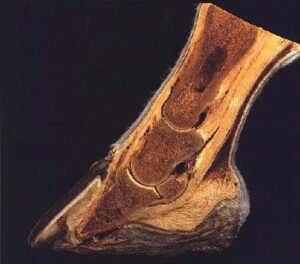

La laminitis equina, también conocida comúnmente como infosura, es una de las enfermedades más dolorosas, graves y potencialmente devastadoras que pueden afectar a los caballos. Consiste en la inflamación y a su vez una disminución del flujo sanguíneo causando el debilitamiento de las láminas, que son los tejidos blandos que actúan conectando el hueso tejuelo (tercera falange) con la pared interna del casco.